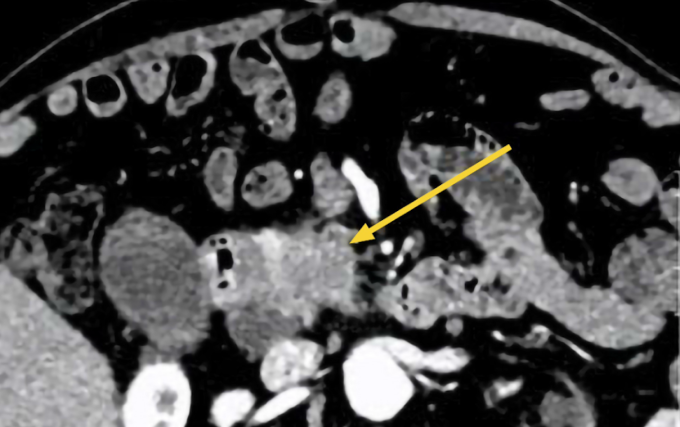

Kết quả siêu âm ổ bụng cho thấy vùng đầu tụy có cấu trúc giảm âm kích thước khoảng 70 mm, kèm phù nề mô xung quanh. Thân, đuôi tụy có một số tổn thương nhỏ hơn. Hình ảnh CT bụng ghi nhận tổn thương tại vùng đầu tụy gây giãn đường mật trong và ngoài gan, bác sĩ nghi ngờ ác tính. Khối u có ranh giới không rõ với đoạn D2 của tá tràng (đoạn đầu của ruột non). Túi mật căng, trong lòng có sỏi, bùn mật, một số hạch quanh đầu tụy, rốn gan.

Chụp CT cho thấy đầy tụy tổn thương (mũi tên vàng)của ông Hưng. Ảnh: Bệnh viện Đa khoa Tâm Anh